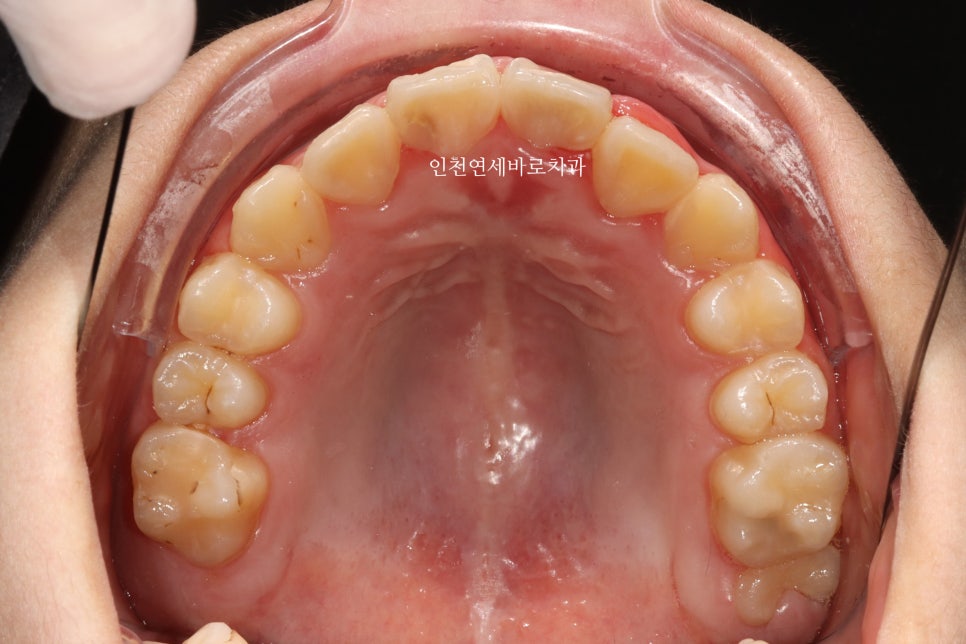

그리고 올해 12월 초에 병원에 왔을 때의 모습입니다.

100점은 아니지만, 이제는 거의 모든 치아가 배열된 것 처럼 보입니다.